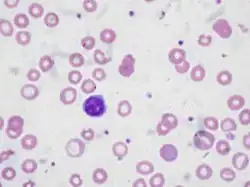

| Blood smear showing iron-deficiency anemia, with small, pale red blood cells | |

Anemia is typically diagnosed on a complete blood count. Apart from reporting the number of red blood cells and the hemoglobin level, the automatic counters also measure the size of the red blood cells by flow cytometry, which is an important tool in distinguishing between the causes of anemia. Examination of a stained blood smear using a microscope can also be helpful, and it is sometimes a necessity in regions of the world where automated analysis is less accessible.

Red blood cell size

In the morphological approach, anemia is classified by the size of red blood cells; this is either done automatically or on microscopic examination of a peripheral blood smear. The size is reflected in the mean corpuscular volume (MCV). If the cells are smaller than normal (under 80 fl), the anemia is said to be microcytic; if they are normal size (80–100 fl), normocytic; and if they are larger than normal (over 100 fl), the anemia is classified as macrocytic. This scheme quickly exposes some of the most common causes of anemia; for instance, a microcytic anemia is often the result of iron deficiency.

Iron-deficiency anemia is the most common type of anemia overall, and it has many causes. RBCs often appear hypochromic (paler than usual) and microcytic (smaller than usual) when viewed with a microscope.